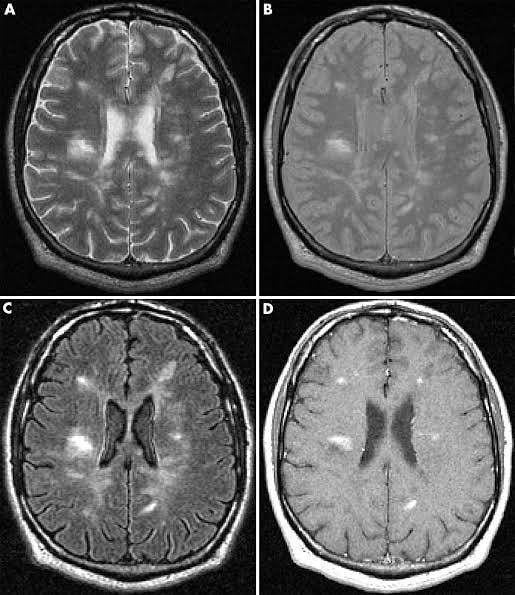

Multiple sclerosis (MS) is a relatively common acquired chronic relapsing demyelinating disease involving the central nervous system, and is the second most common cause of neurological impairment in young adults, after trauma 19. Characteristically, and by definition, multiple sclerosis is disseminated not only in space (i.e. multiple lesions in different regions of the brain) but also in time (i.e. lesions occur at different times). A number of clinical variants are recognised, each with specific imaging findings and clinical presentation. They include: classic multiple sclerosis (Charcot type) tumefactive multiple sclerosis Marburg type (acute malignant) Schilder type (diffuse cerebral sclerosis) Balo concentric sclerosis Clinical presentation is both highly variable acutely, as a result of varying plaque location, as well as over time. Examples of common clinical features include: 🟠brainstem and cranial nerve involvement: optic neuritis internuclear ophthalmoplegia (often bilateral) trigeminal neuralgia diplopia (e.g. due to abducens nerve palsy) vertigo 🟢cerebellum involvement: ataxia and gait disturbance oscillopsia 🔵cerebrum and spinal cord involvement: limb sensory loss or paraesthesias upper motor neurone signs Lhermitte sign urinary incontinence 🟣others: fatigue depression Uhthoff phenomenon: heat and exercise worsen symptoms cognitive decline